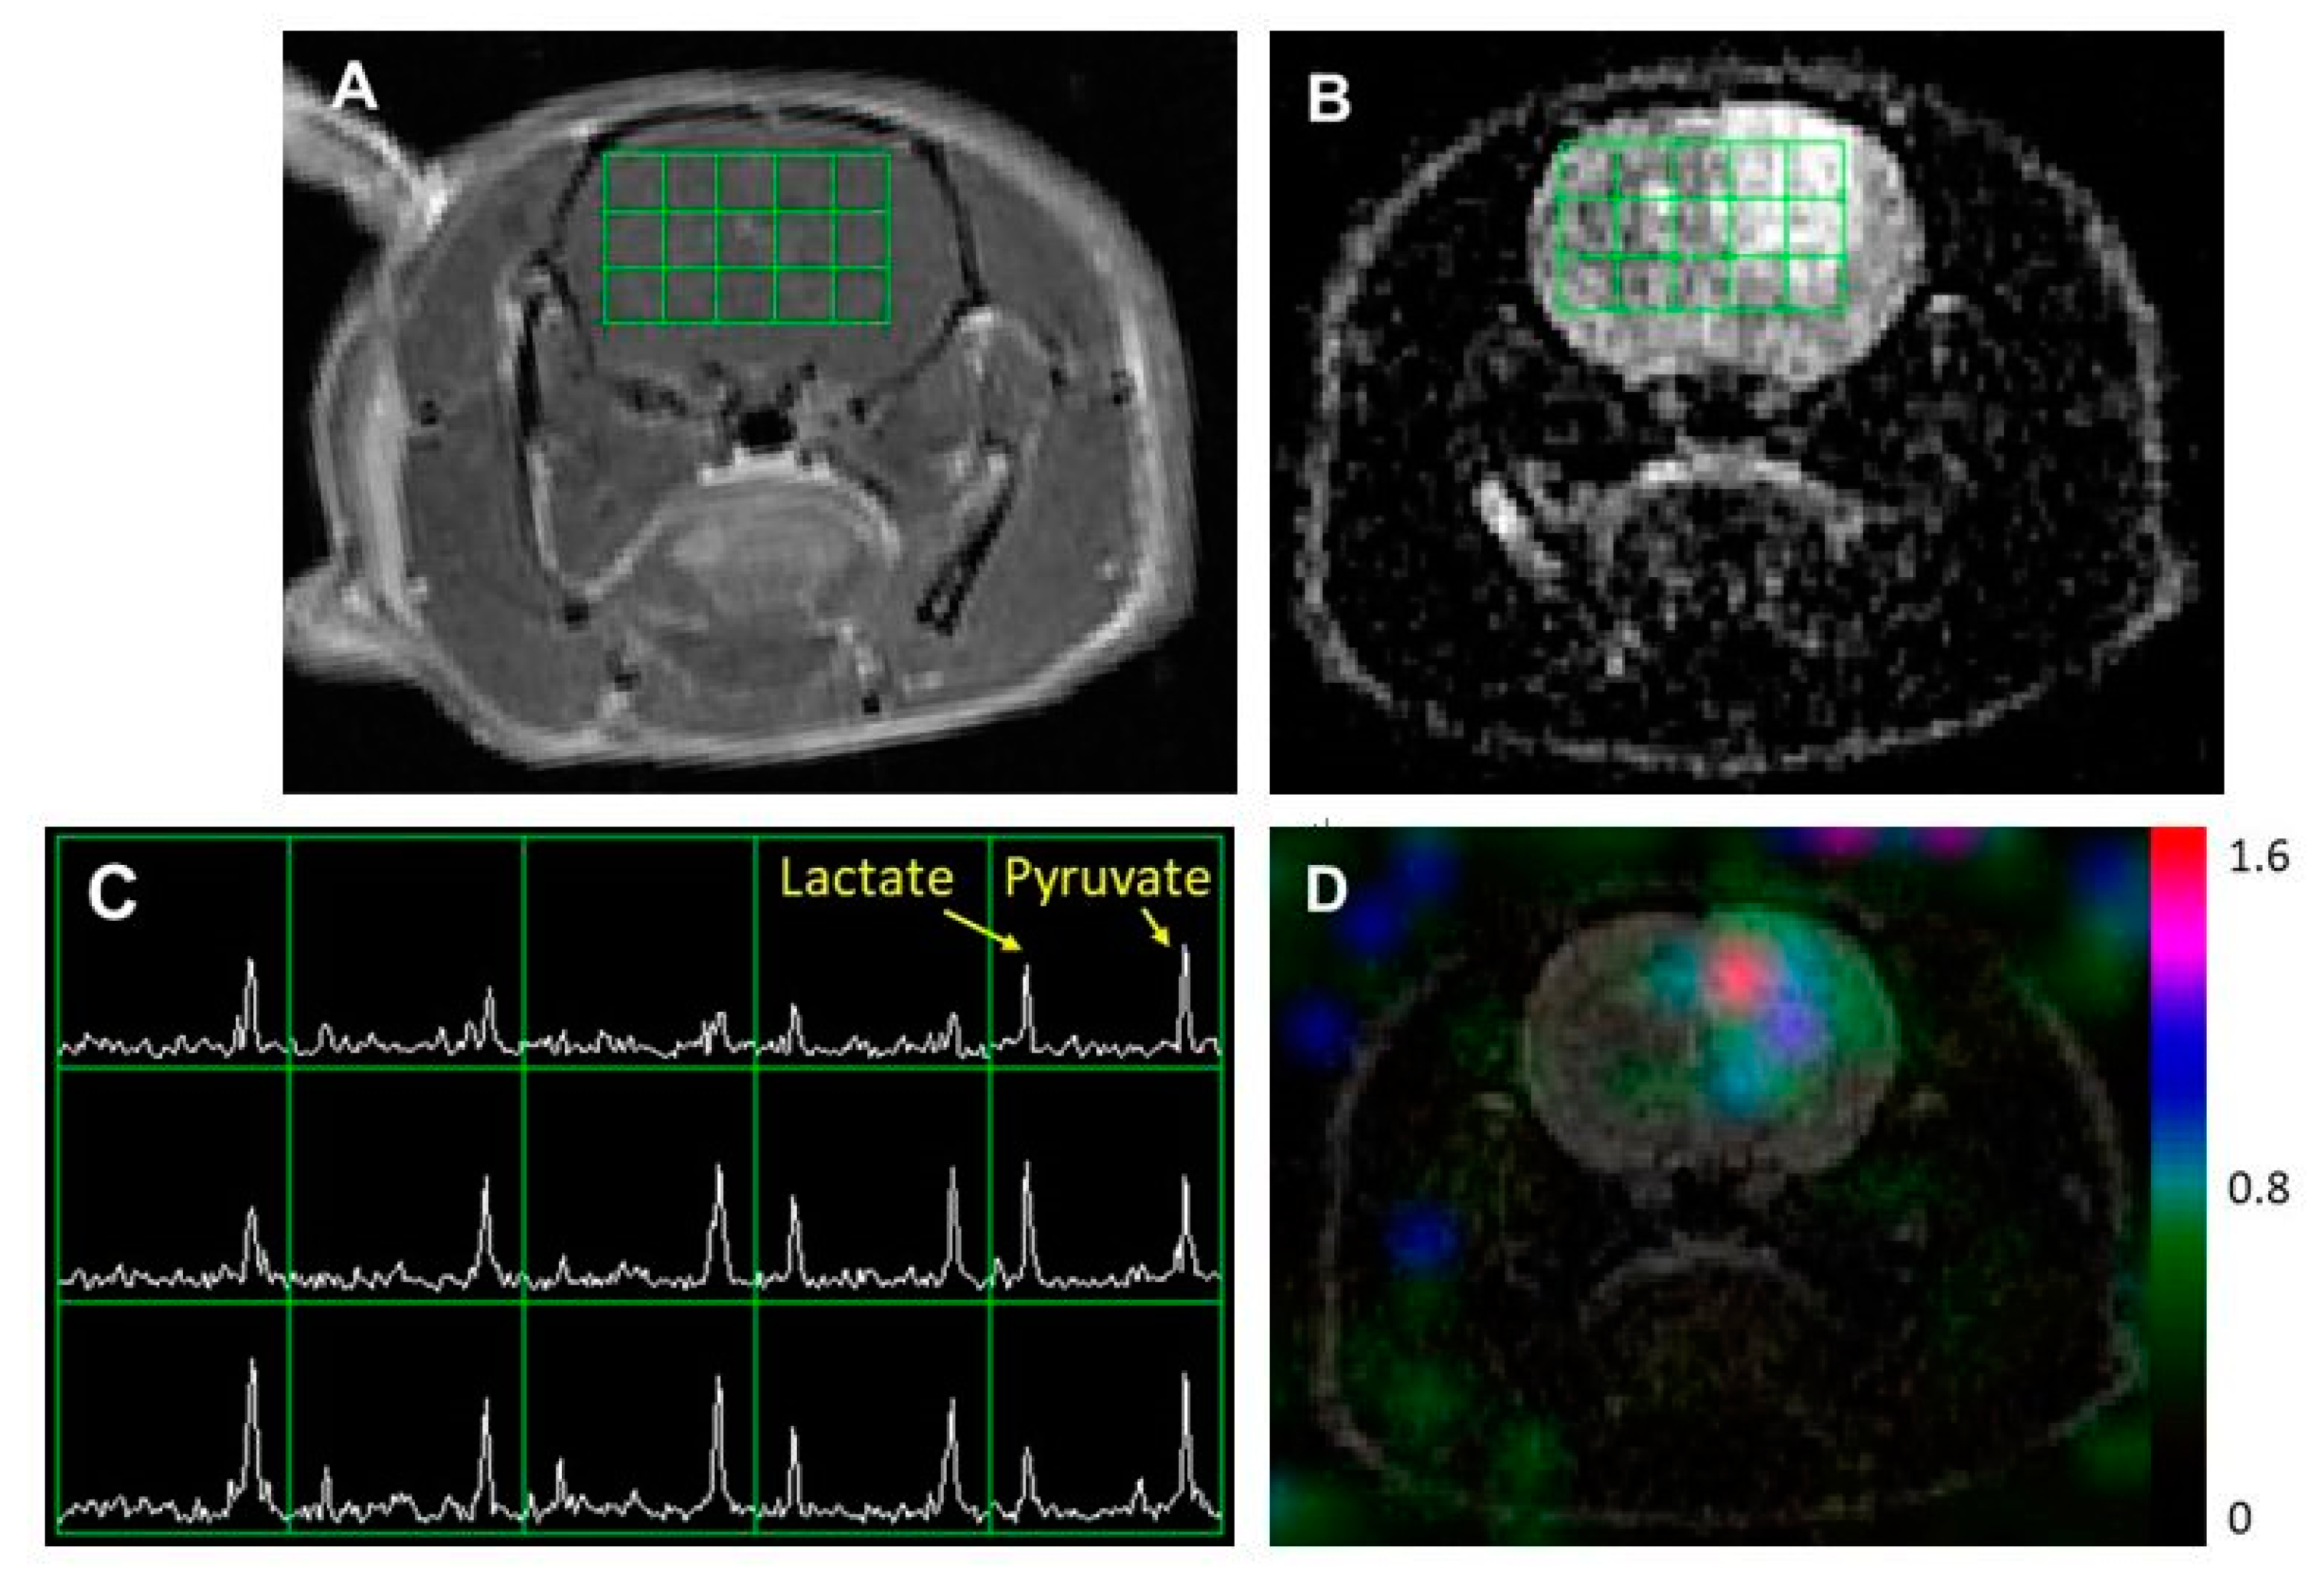

Figure 1 shows an example of 1H and 13C imaging data from a rat model of glioblastoma. The post-gadolinium (Gd) T1-weighted image (T1WI, Figure 1A) and T2-weighted image (T2WI, Figure 1B) showed typical morphological features of high-grade gliomas: a contrast-enhancing lesion in post-contrast T1WI and hyperintensity in T2WI. The green grids on top of T1WI and T2WI represented the array of 13C metabolic data over the brain, with an in-plane voxel resolution of 2 × 2 mm, which corresponded to the MRSI spectra in Figure 1C. Each voxel in Figure 1C contains the hyperpolarized 13C pyruvate signal and its metabolic product, lactate. Figure 1D is a color overlay map of the ratio of lactate to pyruvate (Lac/Pyr), which shows a high level of Lac/Pyr in the enhancing lesion.

An example of MR imaging data from a rat model of glioblastoma. A post-gadolinium T1-weighted image (A) and T2-weighted image (B) showed the typical features of a high-grade glioma: contrast enhancement in the post-contrast T1-weighted image and hyperintensity in the T2-weighted image. The grid in (A,B) represents the array of 13C spectroscopic imaging data over the brain, with an in-plane voxel resolution of 2 × 2 mm (C). Each voxel in (C) contains the hyperpolarized 13C pyruvate signal and its metabolic product, lactate. The color overlay map of the ratio of lactate to pyruvate in (D) shows a highly elevated level of lactate in the enhancing lesion.